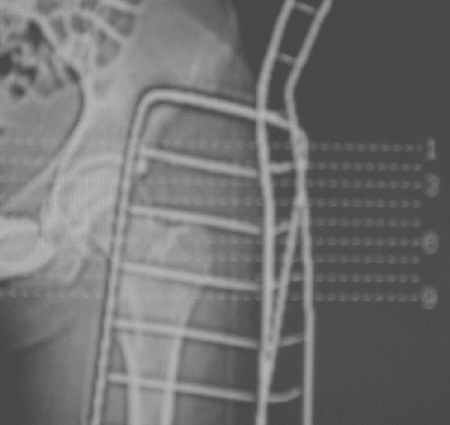

Уважаемые коллеги! Спасибо всем, кто откликнулся на обсуждение. На сегодня доделаны боковые снимки и КТ. Компьютера с возможностью 3D реконструкции на Камчатке нет. Официальное заключение по имеющимся сканам: имеется оскольчатый перелом головки бедра с фрагментацией ее передне-нижнего отдела. Соотношения в суставе в настоящее время правильные. Кзади и выше него в мягких тканях - отдельно лежащий костный фрагмент 15х25 мм (вероятно от головки).

Досылаю на форум КТ и R-граммы. У самого, откровенно говоря, сомнения остаются относительно того, что это не фрагменты вертлужной впадины. В последнем случае, думаю надо оперировать, а если это фрагменты головки из ненагруженной зоны - то не уверен. Какие есть мнения, в том числе и по срокам рагрузки сустава? Главный травматолог Камчатского Военно-морского госпиталя Булахтин Юрий Алексеевич Больного сейчас ничего не беспокоит. Уложен на щит, иммобилизация деротационным сапогом.

Прямой 19.05